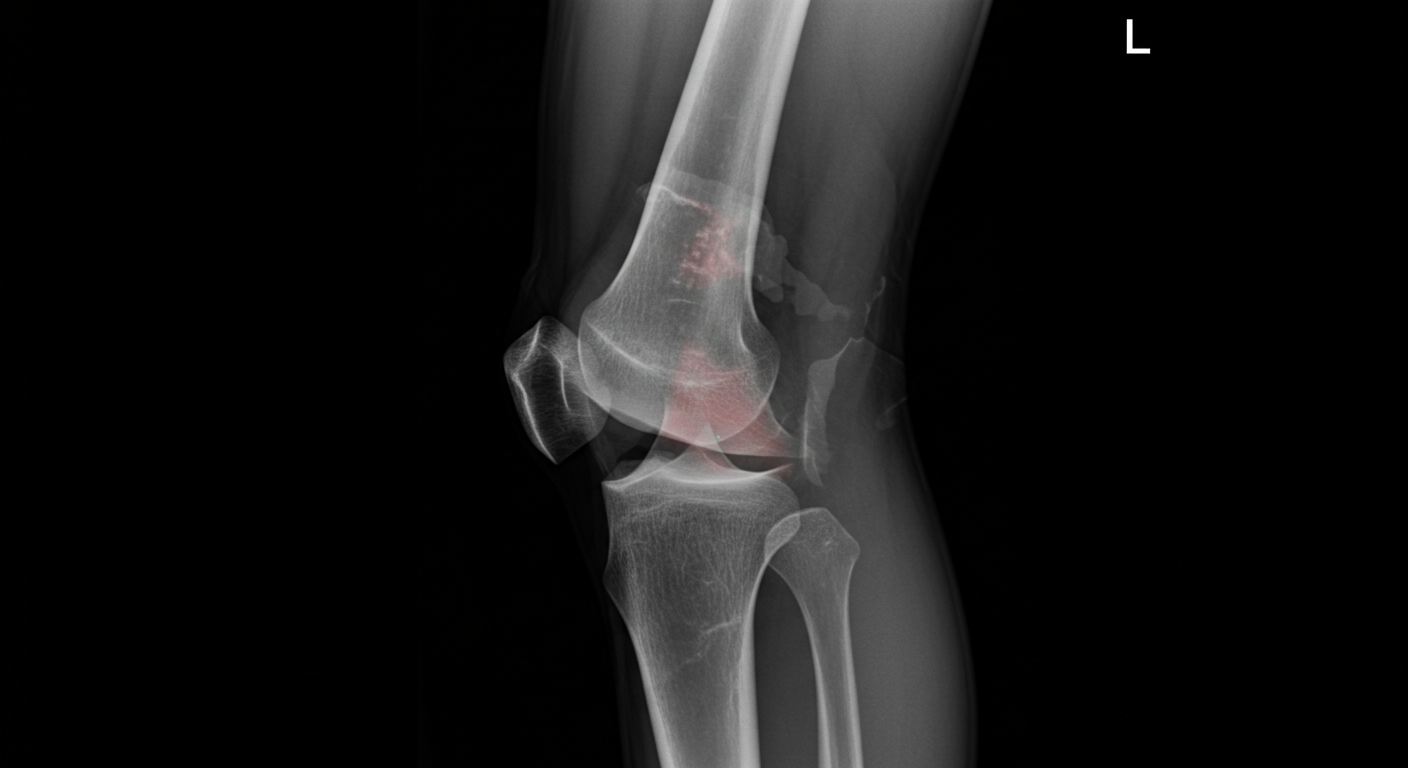

Tearing my MCL, PCL, and meniscus felt like everything had stopped.

But that chapter forced something deeper: discipline, patience, structure, emotional control, and the ability to rebuild identity through action.